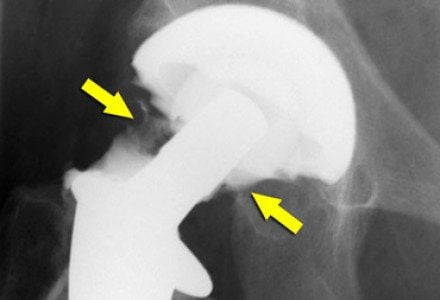

- вывих и ослабление бедренного соединения. Вывихнутый сустав ставится на место под наркозом;

- инфицирование. Первый признак такого осложнения – высокая температура, покраснение, отечность прооперированной зоны. Прием антибиотиков – обязательный элемент послеоперационного периода. Однако в 1 случае из 200 заражение все же наступает, тогда имплантат удаляется, инфицированная зона зачищается, затем устанавливается новый протез;